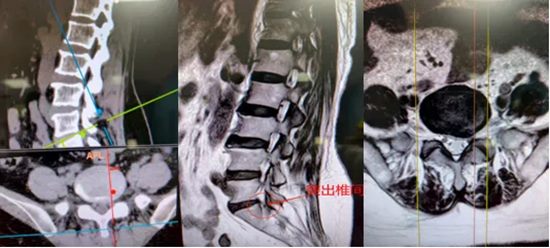

经详细查体,发现真正的“责任节段”并非腰4/5,真正原因竟是腰5骶1节段左侧侧隐窝处,椎间盘突出下垂严重压迫骶1神经根。

明确问题后,实施了“椎间孔镜下腰5骶1椎间盘突出摘除术”。